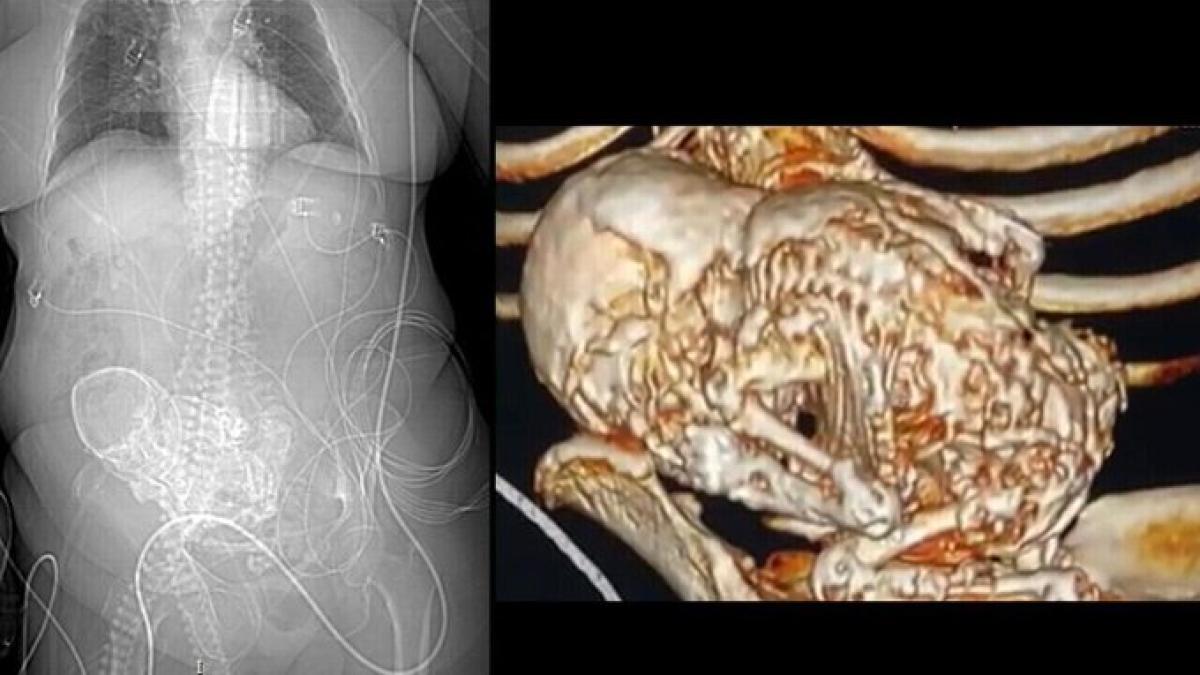

La anciana acudió al Hospital Regional Dr. José de Simone Netto, en la ciudad de Ponta Porã, el pasado 14 de marzo con una infección grave y le realizaron una tomografía, momento en el que el equipo médico descubrió que la mujer tenía un «feto calcificado».

Se trata de una condición rara denominada ‘litopedia’, que significa «bebé de piedra» y es causada por un óvulo que se fertiliza fuera del útero y deriva en la muerte del feto y su posterior calcificación.